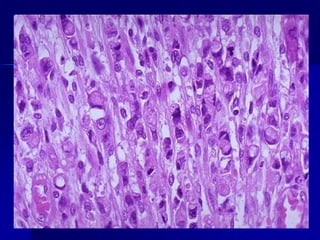

CARACTERÍSTICAS

ANAPLÁSICAS DE

TUMORES MALIGNOS

Tumor anaplásico que muestra variaciones celulares y nucleares

en el tamaño y la forma

Tumor anaplásico quemuestra variaciones celulares y nucleares en el tamaño y la forma